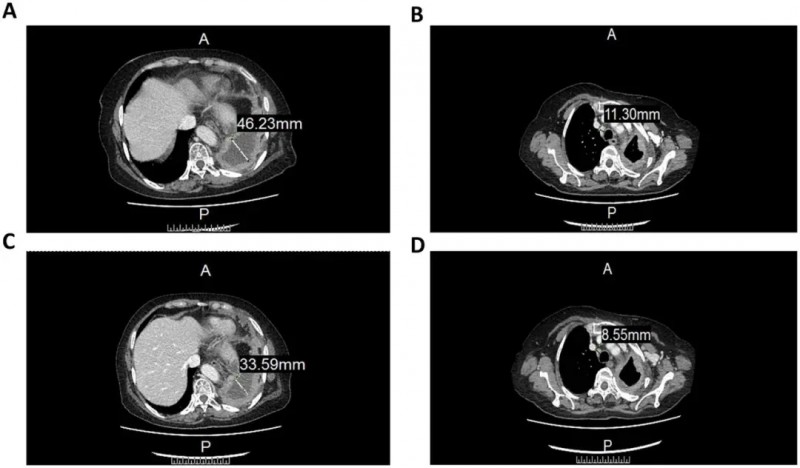

结果显示:治疗后CT检查发现肿瘤病灶显著缩小、胸腔积液也有所减少。具体表现为前气管-后腔静脉间质区淋巴结由11.3mm缩小至8.55mm(详见下图B/D),左肺包裹性胸腔积液由46.22mm减少至33.59mm(详见下图A/C)。

▼CCCR-NK92细胞治疗前后CT图像对比